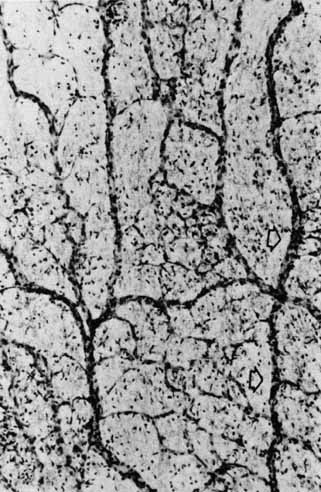

Fig. 3 Light micrograph of human peripheral retina including portion of the choroid (Richardson's methylene blue/azure II stain mixture, 40× objective, Courtesy of Scheie Eye Institute). Inner limiting membrane (arrow): (1) nerve fiber layer, (2) ganglion cell layer, (3) inner plexiform layer, (4) inner nuclear layer, (5) outer plexiform layer, (6) nuclei of photoreceptors (outer nuclear layer), (7) rod and cone inner segments, (8) rod and cone outer segments, (9) pigment epithelium.

A cross section of a low-power histologic preparation of the retina in the region immediately peripheral to the area centralis shows it to have nine layers (Fig. 3). From internally (the side toward the vitreous), the layers are as follows: